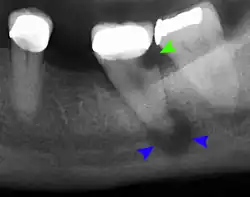

- Radiographs utilized to find dental caries and bone loss laterally or at the apex.

Decay (green) with apical abscess (blue) -

Gutta-percha point indicating abscess origin